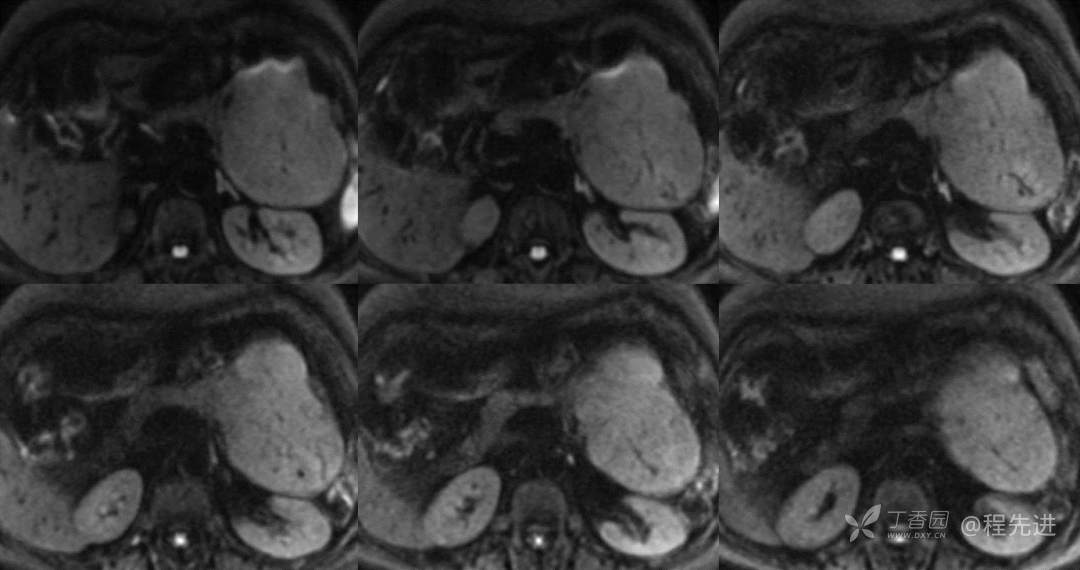

动态增强

动脉期

门脉期

延迟期

汇总对比